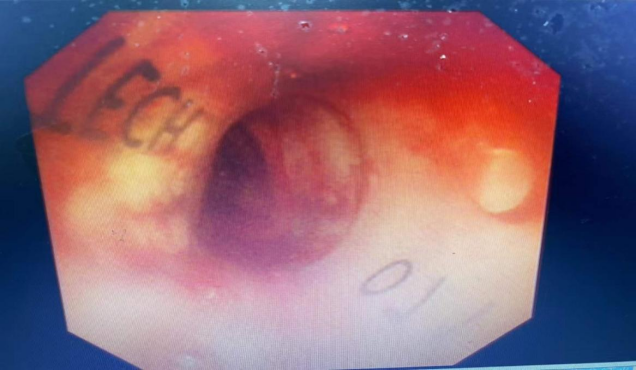

近日,自治区南溪山医院呼吸与危重症医学科二病区主任、博士屈东明带领科室介入团队在全麻硬镜下,成功开展一例沙漏状硅酮支架植入术。这是该院首例沙漏状硅酮支架植入,标志着呼吸内科支气管镜介入治疗技术又上新台阶。

患者是一位78岁老年男性。因“咳嗽并气促1月余”入院,胸部CT发现纵膈占位并侵犯气管上段重度狭窄,结合患者病史、胸部CT及常规气管镜所见,经充分讨论与研究,决定予行全麻硬镜下沙漏状硅酮支架植入。呼吸二区主任屈东明博士现场亲自操作,介入团队和麻醉科及内镜中心通力合作,过程顺利,支架位置固定良好。术后患者氧合明显改善,活动耐力显著提高,已脱离吸氧自由呼吸,为下一步治疗争取了大量时间,助力患者早日康复。